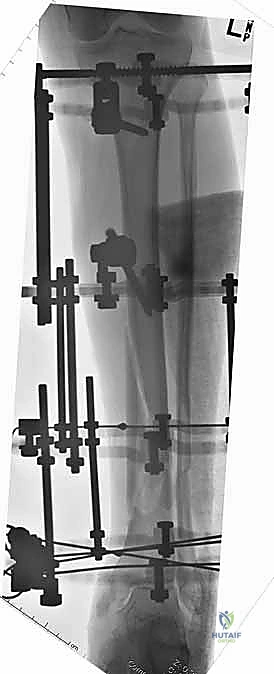

باستخدام جهاز الأشعة السينية المتحرك داخل غرفة العمليات (C-arm)، يقوم الدكتور هطيف بتحديد الأماكن الآمنة (Safe Corridors) لإدخال الدبابيس المعدنية (Schanz pins). هذه الأماكن يتم اختيارها بدقة متناهية لتجنب إصابة الأعصاب أو الأوعية الدموية الحيوية في الساق. يتم عمل شقوق صغيرة جداً في الجلد وإدخال الدبابيس في العظم السليم فوق وتحت الكسر.

5. تركيب الإطار الخارجي (Frame Assembly)

بمجرد أن تصبح العظام في الوضع الصحيح، يتم توصيل الدبابيس البارزة من الجلد بقضبان معدنية (Rods) أو إطار دائري باستخدام مشابك (Clamps) خاصة. يتم إحكام ربط هذه المشابك لتثبيت العظام بقوة ومنعها من الحركة تماماً.